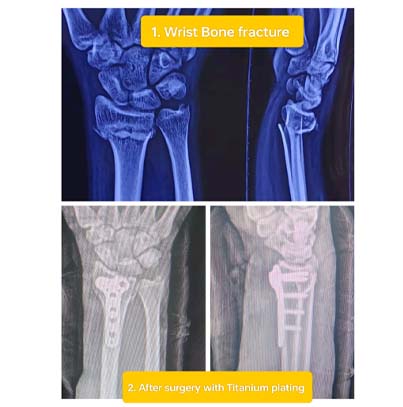

• Imaging Tests: X-ray, MRI to guide surgery